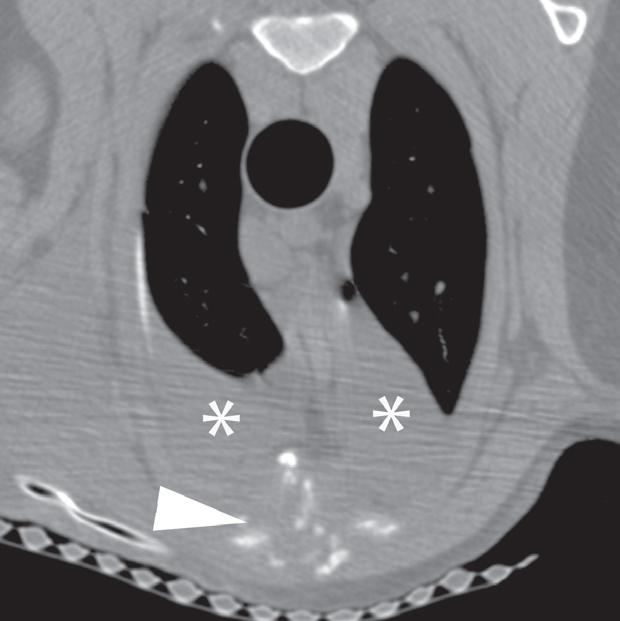

Rycina 4.1.5. Osteomyelitis mostka (pies) TK

Badanie wykonano u 18-miesięcznego, kastrowanego samca dobermana. Ryciny a i b przedstawiają kolejne obrazy poprzeczne doczaszkowej części klatki piersiowej w orientacji doczaszkowo-doogonowej. Widoczne jest nieuorganizowane niszczenie kości obejmujące drugi segment mostka (a–d – grot strzałki). Obecne jest również złamanie patologiczne (c – grot strzałki). Obustronnie widać umiarkowaną ilość płynu w jamie opłucnej w zgodnej grawitacyjnie przestrzeni opłucnowej (a, b – gwiazdki). Biopsja kości potwierdziła przewlekłe neutrofilowe zapalenie kości i szpiku, a cytologia płynu opłucnowego wykazała obecność zapalenia ropnego